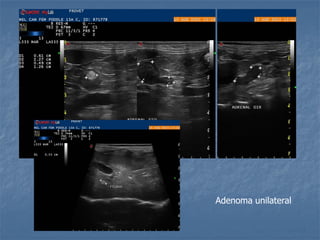

Adenoma unilateral

 Hiperadrenocorticismo - Neoplásico: *massa unilateral, ecotextura heterogênea e atrofia contra lateral * pode haver presença de massas adrenais não funcionantes e ausência de atrofia contra-lateral * pode haver massa adrenal bilateral * pode haver pouca atrofia contra-lateral * pode haver presença de trombos metastáticos na V.C.C.